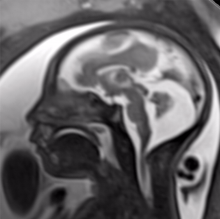

2. MRIs During Pregnancy Are Safe, But Gadolinium Scans May Increase Risk to Fetus